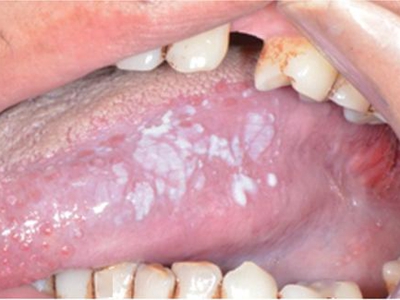

舌头

白斑

口腔白斑病舌侧有毛状白斑图

口腔白斑病在舌腹发作,表现为大片白斑,与周围的边界清晰,形状不规则,白斑的表面高低起伏,状如白色皱纸,基底柔软很像毛发。